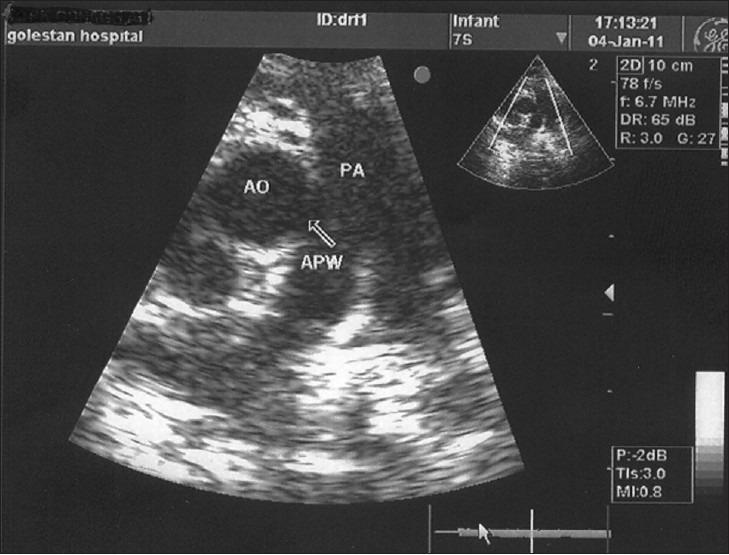

One of the rarest congenital heart diseases that results from a defect between the main pulmonary artery and the proximal aorta is named aortopulmonary window (APW). Such abnormality could be isolated, but in fifty percent of patients may be associated with other cardiac abnormalities, including arch abnormalities, specifically coarctation of the aorta, interrupted aortic arch, tetralogy of fallot, and atrial septal defect (ASD). Surgical closure or catheter-delivered devices is recommended in all patients with APW and should be performed after diagnosis as soon as possible to prevent irreversible pulmonary vascular disease. In the current era, early mortality following repair of simple APW is low and depends on the presence of associated lesions, especially interrupted aortic arch. We report an 8-month-old boy with APW who was referred to our center by respiratory symptoms and heart murmurs.